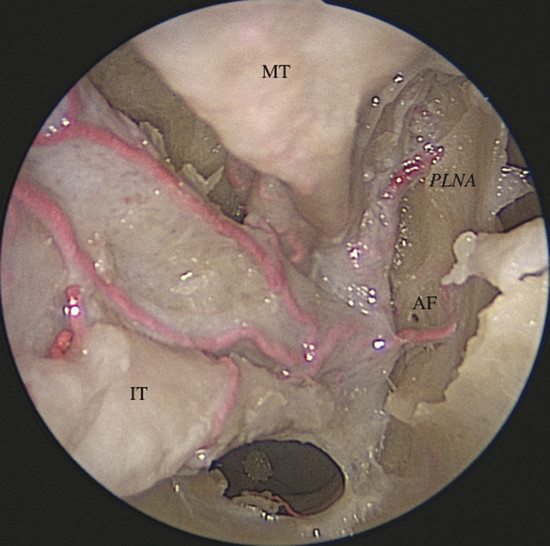

It gives off two main branches, the posterior lateral nasal artery (PLNA) and the posterior septal artery (PSA), 1 , 2 which can be divided into one or two trunks medial to the ethmoidal crest, before or after crossing the sphenopalatine foramen. It is rarely possible to identify more than two trunks. 1 , 3 The PLNA supplies the region of the lateral nasal wall giving off branches to the inferior turbinate (inferior turbinate artery), middle turbinate (middle turbinate artery), mucosa of the fontanelle, and to the mucosa of the maxillary sinus 4 (Fig. 3‑3, Fig. 3‑4). In approximately 20% of cases this artery supplies the superior turbinate. 5 The inferior turbinate artery enters a bony canal and runs anteriorly along the turbinate. It usually gives off two terminal branches, within or adjacent to the bone, supplying the mucosa of the turbinate (Fig. 3‑5). The artery gives off several small vessels to the maxillary sinus and to the ethmoidal complex. The middle turbinate artery gives off several branches, some of which run along the medial surface of the turbinate whereas the other branches supply the lateral turbinate surface and anterior ethmoidal complex (see Fig. 3‑3).